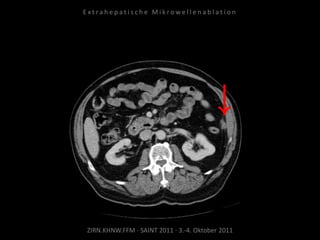

Bildgebung vor MWA:

CT vom 14.07.2010

Metastase lateral der linken Niere

nahe Colon descendens progredient.

Situation:

Metastasierung über längeren Zeitraum

lokal begrenzt,

1 Metastase progredient.

Organnahe Lage in unmittelbarer

Nachbarschaft zur linken Niere bzw. zum

Colon descendens.